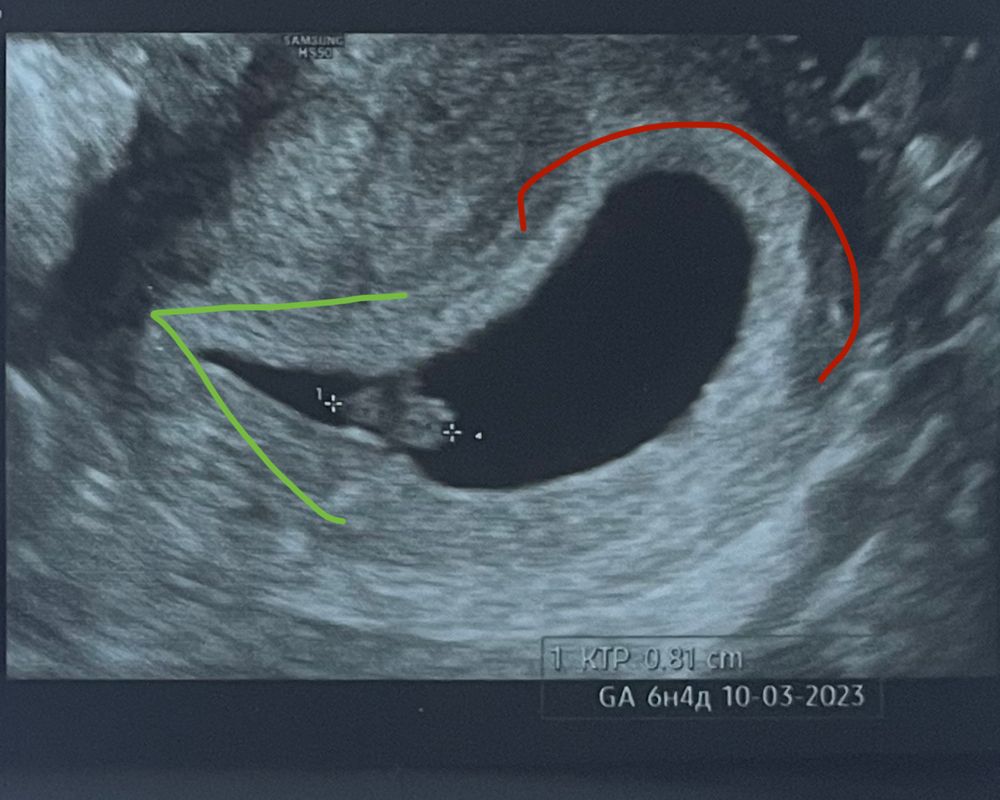

3. На узи необходимо найти дно и шейку матки. Дно матки - это самая широкая ее часть, отмечена красным. Шейка матки самая узкая часть, отмечена зеленым. Это очень важный момент, если вам печатают фото у врача и все стороны одинаковые, то обязательно спросите где какая часть. Без понимания этого этапа дальше все бесполезно.

После того как вы определили, поверните фото так, чтобы шейка была внизу, а дно наверху, таким образом.

Теперь повернув узи в правильном виде, вы как бы смотрите на себя в анфас.

4. ХОРИОН. Далее необходимо понять где находится крепление предполагаемой планцента и как располагается хорион. Учитывая что он кольцевидный и идёт вокруг амниотического пузыря.

Немного биологии. Хорион это такие светлые участки видимые на узи располагаются вокруг чёрной полости. И в какой то части полости у оболочки этот хорион как бы рассеивается и этого белого участка сильно больше.

Обратите внимание что у хориона есть граница. И на качественном узи ее видно.

На данном узи можно будет видеть что белый участок рассеивается в правую сторону. Это говорит что крепление плаценты с правой стороны.

ЕСЛИ ХОРИОНА СИЛЬНО БОЛЬШЕ ПО ПРАВОЙ СТОРОНЕ - то это говорит о ДЕВОЧКЕ!

ЕСЛИ ХОРИОНА СИЛЬНО БОЛЬШЕ ПО ЛЕВОЙ СТОРОНЕ - то это говорит о МАЛЬЧИКЕ!